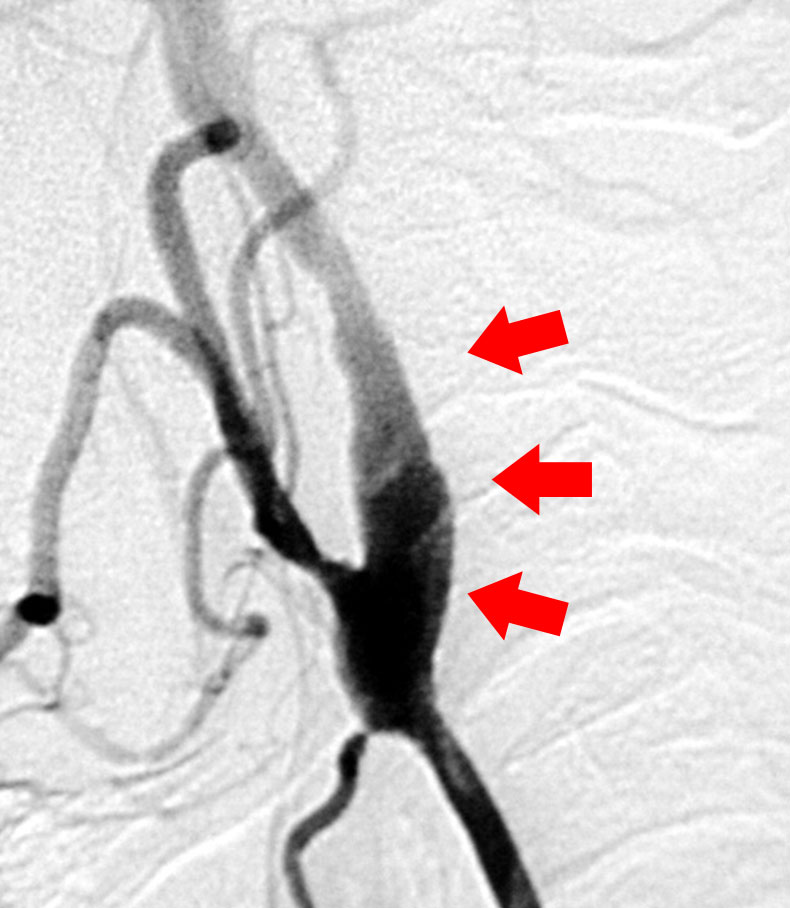

さて当科では脳梗塞予防手術を積極的に行っています。最近食生活の欧米化で内頚動脈起始部狭窄症が増加しています。この病気に対しては外科的治療と血管内治療がありますが、当科では主に外科的治療によって内頚動脈の厚くなった内膜を剥離して血管を広げ、脳梗塞を予防しています(図9、10)。

すでに詰まってしまっている患者さんに対しては症状が軽い場合であれば、頭蓋内血管と頭蓋外血管とのバイパス手術を行い、症状の悪化を予防しています(図11,図12,図13)。